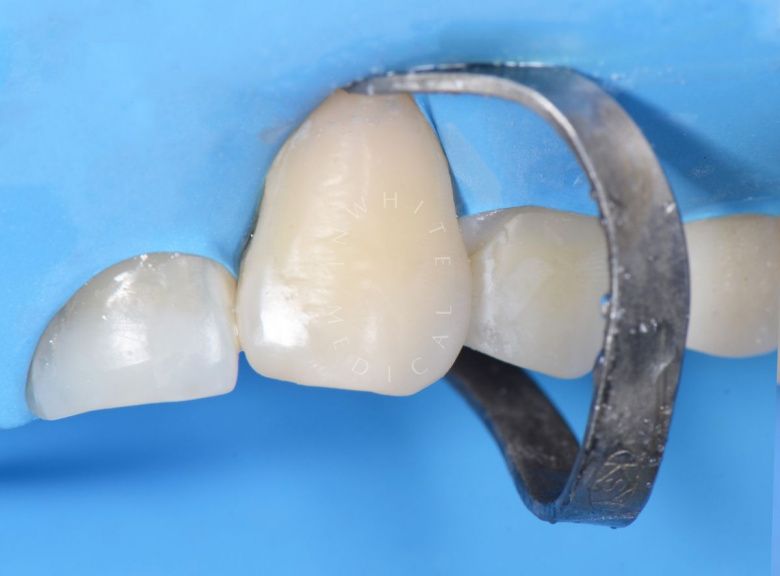

Лечение скрытого кариеса под старой пломбой

Лучшие стоматологические клиники. Лечение скрытого кариеса под старой пломбой  - после процедуры